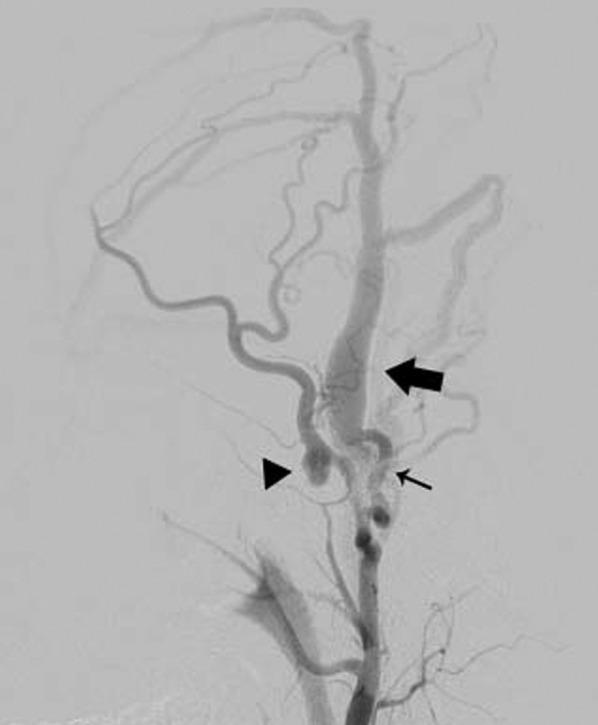

Traumatic arteriovenous fistula (AVF) of the superficial temporal artery (STA) is rare. We report a case of surgically treated, histopathologically confirmed traumatic AVF of the STA. A 24-year-old male was admitted to our hospital after a traffic accident. Computed tomography scan on admission showed an acute epidural hematoma on the right surface of frontal lobe, which was emergently treated by surgical evacuation. One month later, he was aware of pulsatile tinnitus around the left ear. Digital subtraction angiogram showed an AVF, mainly fed by the left STA. After total removal of the fistula, his tinnitus immediately disappeared. Histopathological examination demonstrated that the artery was connected to the vein through the thin-walled vessels lacking internal elastic lamina and muscularized media, suggesting that the connecting vessels were newly formed.

颞浅动脉创伤性动静脉瘘(AVF)较为罕见。我们报告一例经手术治疗、组织病理学确诊的颞浅动脉创伤性AVF病例。一名24岁男性在交通事故后入院。入院时的计算机断层扫描显示右额叶表面急性硬膜外血肿,遂紧急行手术清除。1个月后,他感觉到左耳周围有搏动性耳鸣。数字减影血管造影显示一个AVF,主要由左颞浅动脉供血。瘘管完全切除后,他的耳鸣立即消失。组织病理学检查表明,动脉通过缺乏内弹性膜和肌化中膜的薄壁血管与静脉相连,提示这些连接血管是新形成的。